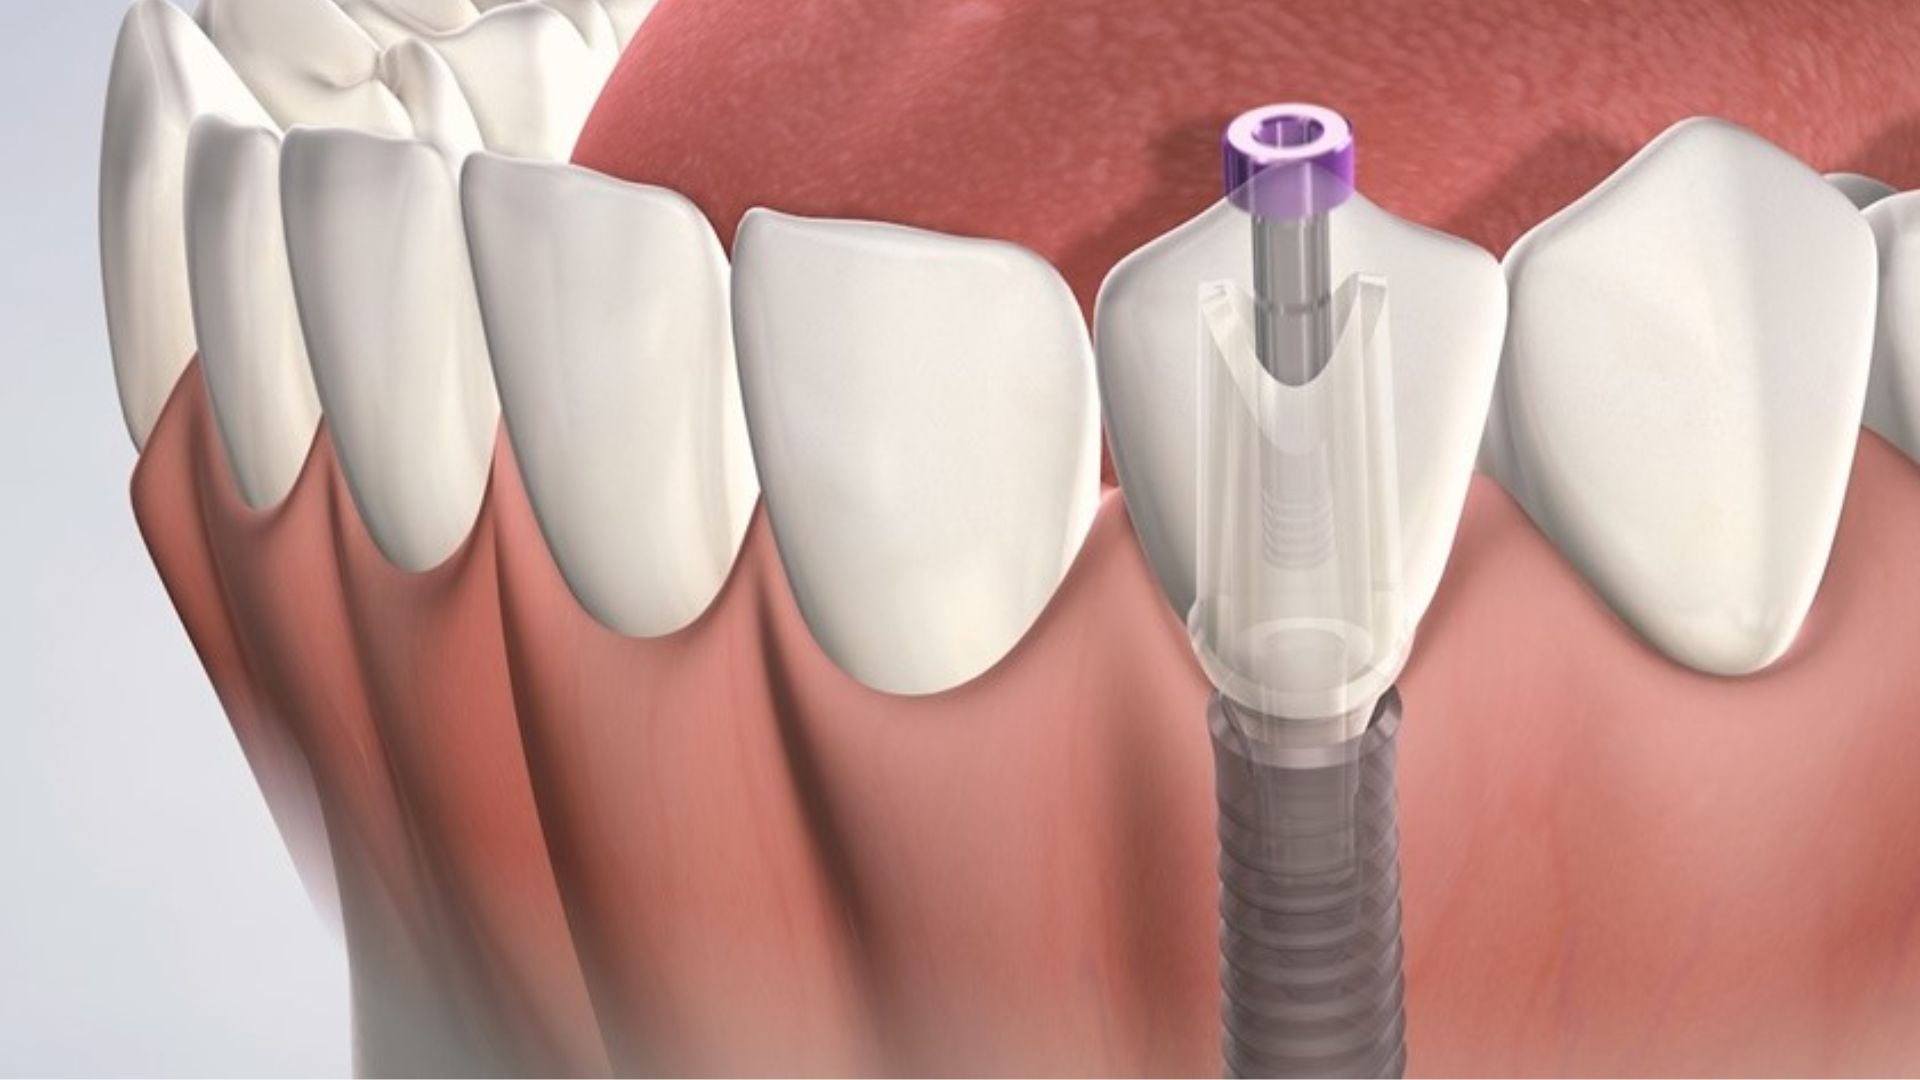

Trồng răng Implant là phương pháp phẫu thuật thay thế chân răng bị mất bằng cách đặt trụ implant vào trong xương hàm. Sau đó, bằng cách lắp răng sứ, bạn sẽ có được những chiếc răng mới có cấu trúc và chức năng ăn nhai giống như răng tự nhiên của bạn.

Bước 2: Tiến hành phẫu thuật cấy ghép Implant

Thời gian phẫu thuật đặt trụ implant vào xương hàm mất khoảng 30 đến 60 phút cho mỗi trụ. Thời gian thực hiện trồng răng implant mất bao lâu tùy thuộc vào chuyên môn của bác sĩ và kỹ thuật cấy ghép.

Tại các nha khoa, ca phẫu thuật cấy ghép implant được thực hiện bởi các bác sĩ có trình độ chuyên môn cao, sử dụng công nghệ và thiết bị cấy ghép mới nhất nên trồng răng implant nhanh nhất chỉ khoảng 20 phút cho một ca cấy ghép.

Công đoạn cuối cùng là gắn răng sứ cố định trên implant. Thời gian gắn răng sứ sẽ dao động từ khoảng 20 – 40 phút/ 1 răng.